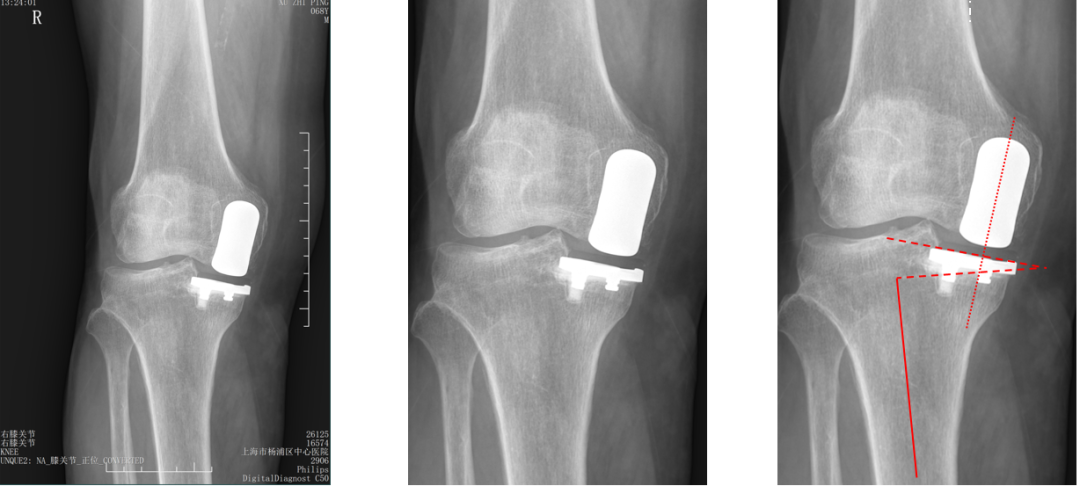

三、胫骨假体下沉翻修

外侧间室OA行LUKA,术后外伤导致胫骨假体塌陷

胫骨假体翻修术(保留股骨假体)

四、胫骨假体过度前倾翻修

LUKA术后胫骨假体过度前倾导致膝关节伸直受限

LUKA术后半年 (20251126)

保留股骨假体胫骨侧翻修

翻修术后 (20251201)